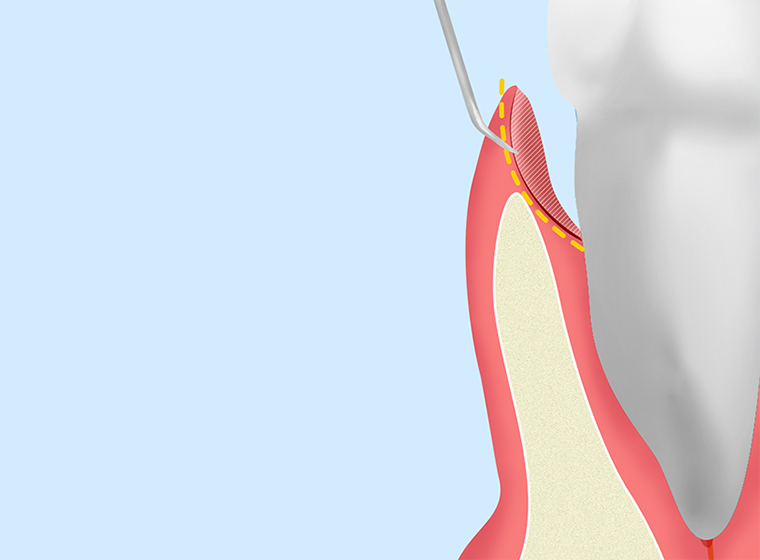

ルートプレーニング

|

スケーリングでは落としきれない歯周ポケットの奥に付着するプラーク(歯垢)や歯石を「キュレット」という器具で除去します。仕上げに歯面を滑らかにして汚れの再付着を防ぎます。 |